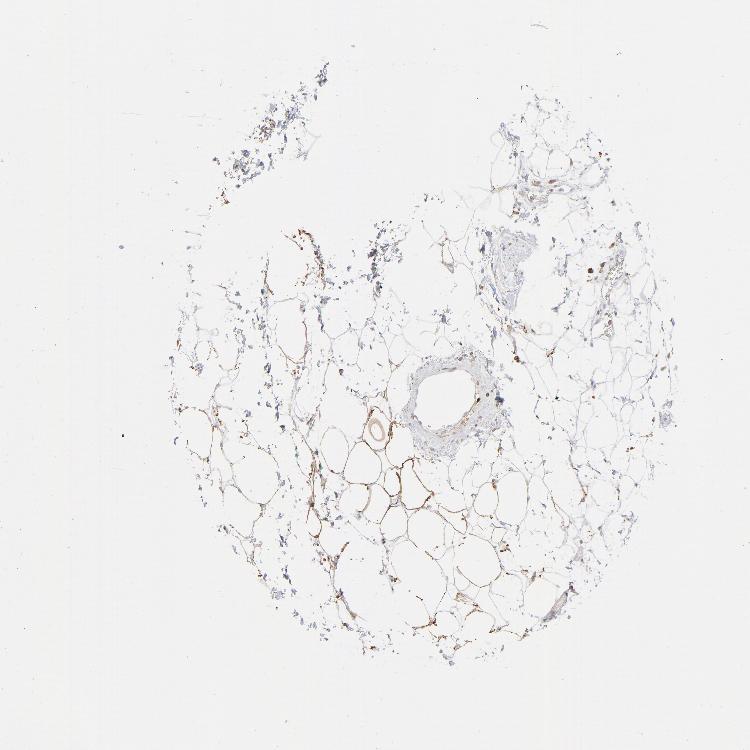

SOFT TISSUE 1 - Antibody stainingi

Antibody staining in the annotated cell types in the current human tissue is reported as not detected, low, medium, or high, based on conventional immunohistochemistry profiling in selected tissues. This score is based on the combination of the staining intensity and fraction of stained cells.

Each image is clickable and will lead to virtual microscopy that enables deeper exploration of all samples and also displays staining intensity scores, fraction scores and subcellular localization as well as patient and tissue information for each sample.

Antibody HPA035330Antibody CAB003677

Fibroblasts MediumNot detected